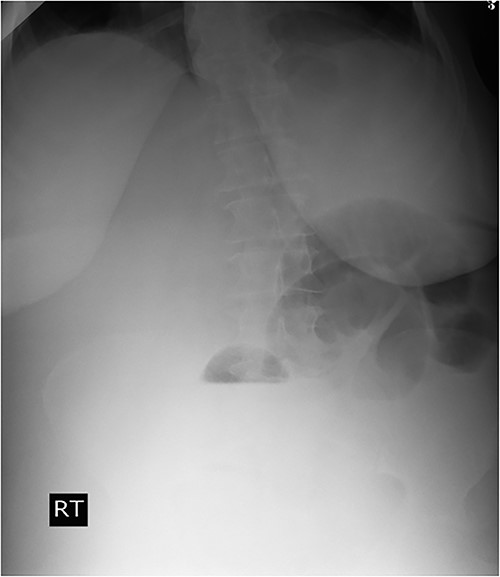

A 53-y-old morbidly obese female patient (BMI = 50) was diagnosed with colicky abdominal pain that progressively worsened over 1 week and became constant, without clear exacerbating or relieving factors. She also complained of fever, constipation, nausea, vomiting and anorexia. Past surgical history was significant for a surgically repaired umbilical hernia 10 y ago. The pain gradually became continuous and more severe, warranting hospital admission for further evaluation. On physical examination, the patient appeared unwell, dehydrated, and severely distressed. Vital signs showed a blood pressure of 100/60 mm Hg, pulse of 90 bpm and a temperature of 38 °C. Oxygen saturation was 95% on ambient air. Abdominal examination revealed midabdominal tenderness with mild abdominal distension, as well as high-pitched bowel sounds. Notably, there was an infected wound measuring 20 cm × 13 cm on the midline of the abdomen with signs of poor healing, tissue necrosis, and foul-smelling discharge (Fig. 1). Rectal examination was inconclusive. Laboratory tests indicated elevated levels of inflammatory markers, including a C-reactive protein (CRP) level of 445 mg/L and a white blood cell count of 30 000/ml. Hemoglobin level was 7.8 g/dl with a mean corpuscular volume (MCV) of 65. Additional abnormal results included a creatinine level of 1.8 mg/dl and a random blood sugar level of 310 mg/dL. Electrolyte levels were normal. Based on the laboratory findings, the LRINEC score was calculated to be 11, suggesting a high risk of NF. A plain abdominal X-ray showed fluid levels in the small intestine but no signs of pneumoperitoneum (Fig. 2). Abdominal ultrasound revealed localised swelling and fluid accumulation in the anterior abdominal wall, with dilated and edematous small intestine loops trapped within. The patient was ultimately diagnosed with strangulated incisional hernia complicated by NF of the abdomen. Management included nasogastric decompression, intravenous fluids and broad-spectrum antibiotics. Subsequently, the patient underwent emergency wound debridement under general anesthesia using a left paramedian laparotomy incision (Fig. 3). During the procedure, necrotic and dark skin, as well as friable subcutaneous tissue, were observed and resected (Figs 4 and 5). Approximately 500 ml of pus and digested food particles were drained from the abdominal wall. Controlled irrigation of the wound with saline was performed, and the strangulated bowel was identified, resected, and a loop ileostomy was created. There was no contamination of the peritoneal cavity. Two surgical drains were inserted, one in the abdominal wall and one in the peritoneal cavity. As the wound was considered contaminated, the fascia was sutured, but the skin edges were approximated and left open for secondary healing (Fig. 6). A temporary cover was applied using a plastic sheath (Fig. 7). The patient was then transferred to the intensive care unit (ICU) for continued postoperative wound care and debridement. On the 7th day, the patient was started on a soft diet and referred to the plastic surgery unit for ongoing wound treatment.

Plain abdominal X-ray demonstrated air-fluid levels of the small bowel.